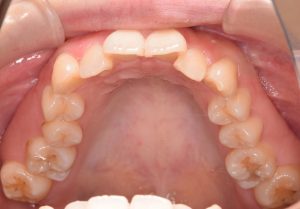

上あご

0000000011

0000000139